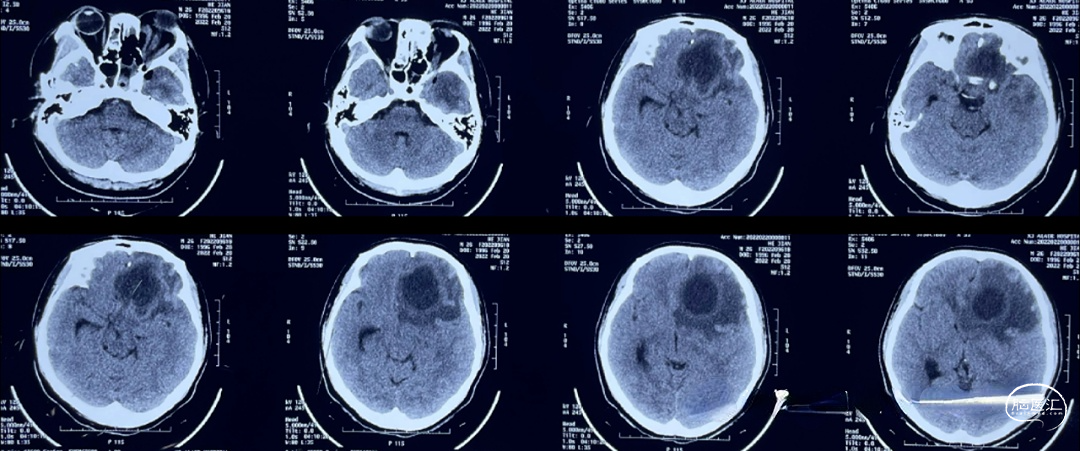

2022.02.02CT:多组鼻窦炎,筛窦为主,感染累及左侧眼眶,眶内组织肿胀;邻近额叶脑组织大片水肿,考虑感染波及颅内

2022.02.03CT:鼻窦感染范围扩大,眶内组织水肿加重,眼球凸出。

2月5日,眼球凸出更为严重,视力急剧下降。脑组织水肿明显,但并无局限性脓肿形成。 继续给予抗生素治疗。

2022.02.05MR:鼻腔,眼眶内感染范围继续扩大,额叶脑组织水肿明显,但并无脓肿形成。

2022.02.07 MR:鼻腔,眼眶内呈现术后改变,额叶水肿范围逐渐局限。

2022.02.20 CT:鼻腔鼻窦内感染引流效果明显,眼眶内引流不佳,组织水肿明显,眼球凸出。左侧额叶脑脓肿形成,直径约为3.5-4cm。